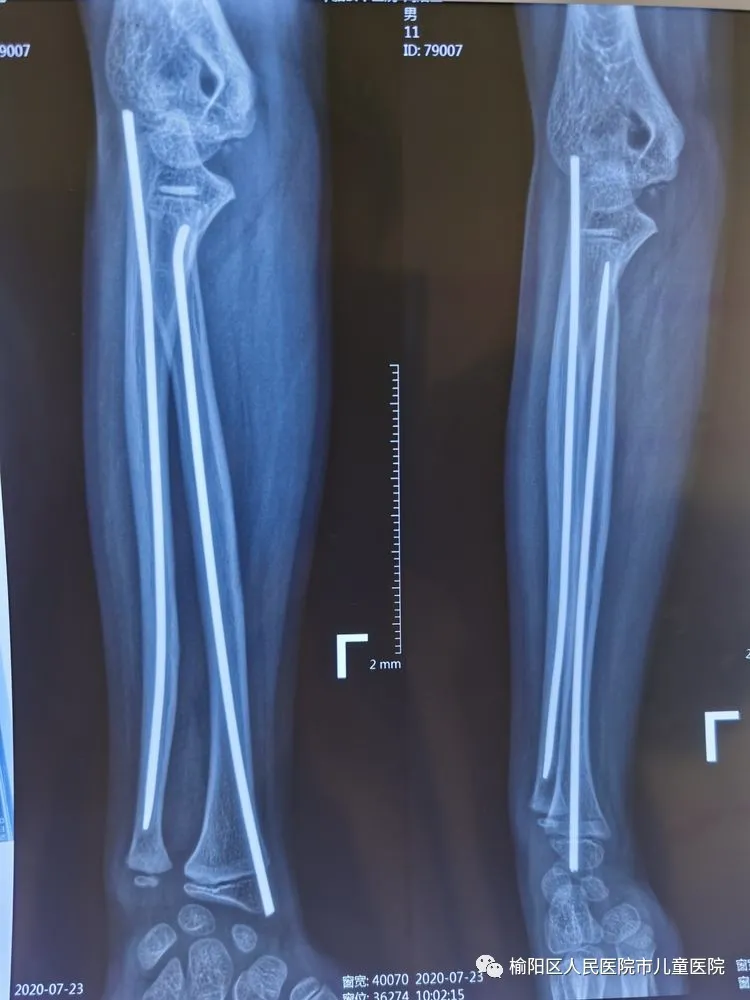

术后5个月,完美愈合。

弹性髄内针治疗小儿四肢骨折优点:手术时间短,创伤小,住院时间短,骨折愈合快,费用低。